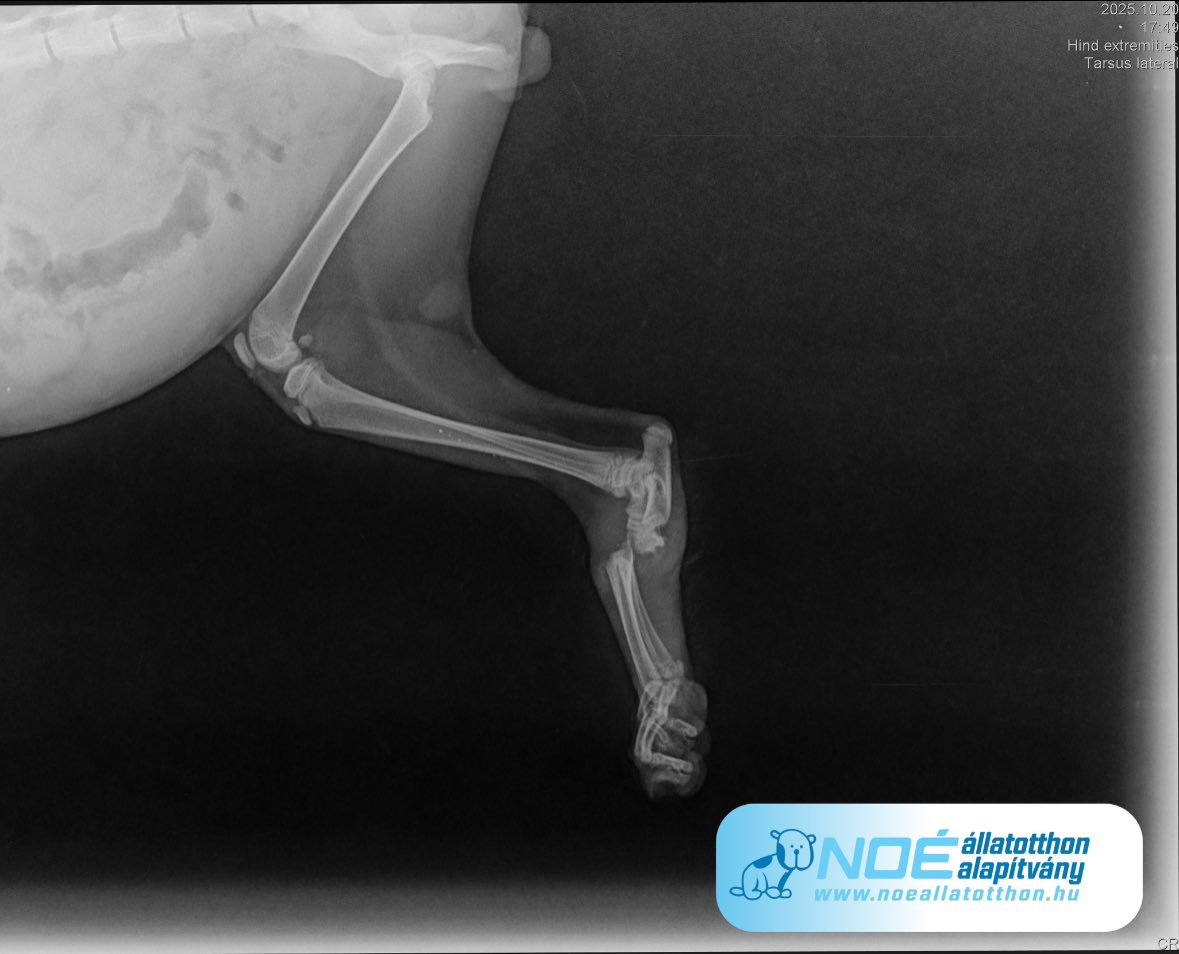

Bendegúz kiscica, aki nyílt lábközépcsont töVIDEO - Bendegúz lézer kezeléseréssel érkezett hozzánk, átesett CsodaBoda dokinál a műtéten. Boda Attila doktor úr húzóhurkokkal rögzítette a törött csontokat es egy speciális kötést is kapott. 🙏

Most pedig nagyon nagyon kell a drukk, hogy rendben gyógyuljon a pici cica lába. 🤞🤞🤞 A sérülése már friss, a nyílt sérülés pedig fertőzött és gyulladt sajnos. 😪